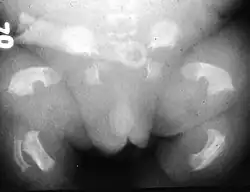

O nanismo tanatofórico ou displasia tanatofórica é uma displasia esquelética do grupo heterogéneo das desordens associadas ao crescimento ósseo, com uma interferência muito significativa no seu tamanho, forma e densidade. Foi muitas vezes confundida com a acondroplasia, no entanto, corresponde a uma manifestação mais severa e letal, que se distingue por micromelia (encurtamento dos membros) grave e que habitualmente resulta na morte do feto in útero ou pouco tempo após o nascimento. Através de conhecimentos e técnicas actuais, alguns casos clínicos do passado viram o diagnóstico alterado de acondroplasia para nanismo tanatofórico.[1][2][3][4][5][6]

Patogénese

Esta patologia provoca uma disrupção generalizada das placas de crescimento com persistência de tecido mesenquimal [4]. As evidências são de uma osteocondroplasia letal, caracterizada por rizomelia (encurtamento das porções proximais), micromelia (extremo encurtamento dos membros), cabeça desproporcionalmente grande com uma área de depressão na porção medial da face, deformações cranianas normalmente provocadas por craniostenose (encerramento prematuro das suturas), esqueleto axial longo comparativamente com o esqueleto apendicular e hipoplasia torácica (redução acentuada do tórax).[7][2][3][4][9]

O Tipo 1 caracteriza-se por rizomelia extrema. A nível craniano, a base do occipital apresenta uma dimensão reduzida, incluindo o foramen magnum, testa proeminente e hipertelorismo ocular (afastamento amplificado das cavidades orbitais). No tórax ocorre platispondilia vertebral (achatamento dos corpos vertebrais) e as costelas apresentam encurtamento com extremidades metafisárias em forma de “chávena”, características que lhe conferem uma configuração mais estreita e em forma de triângulo. Na cintura pélvica, o ílion apresenta uma dimensão mais curta com a margem inferior horizontal, e o ísquion e a púbis possuem uma fisionomia mais larga e curta. Os membros superiores e inferiores caracterizam-se por ossos longos arqueados com diminuição muito significativa do comprimento e com metáfises alargadas. O fémur destaca-se pela sua aparência semelhante a um “auscultador de telefone”. Os membros superiores por vezes podem apresentam dígitos encurtados, verificando-se por vezes sinostose rádio-cubital.[4][6]

O Tipo 2 corresponde a uma manifestação menos severa e mais rara. A alteração mais distintiva observa-se a nível craniano, pela sua forma de “folha de trevo” devido à craniossinostose/oxicefalia (encerramento prematuro da sutura coronal). Os ossos longos apresentam encurtamento, mas uma forma retilínea ao invés de arqueada.[2][3][9][10]